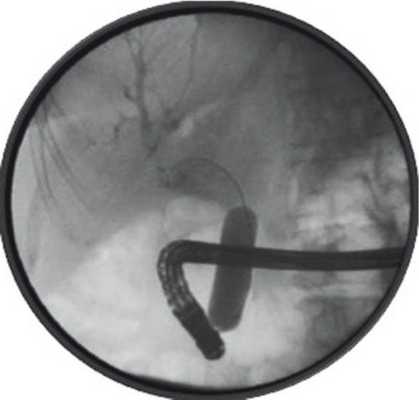

При повторной ЭРПХГ установлено, что в проекции общего печеночного протока находится конкремент диаметром менее 2 см, частично вышедший из желчного пузыря и суживающий просвет ОЖП менее 3 мм. В просвете ОЖП обнаружены 3 конкремента диаметром около 5 мм, которые удалены при помощи корзинки Дормиа. Из-за отсутствия литотриптора соответствующего размера удалить крупный камень не удалось (рис. 2, 3). Рисунок 2. ЭРПХГ. Состояние после ЭПСТ, механической литотрипсии. Фрагмент конкремента в области холецистохоледохеального свища. Хронический калькулезный холецистит. Рисунок 3. ЭРХГ (эндоскопическая ретроградная холангиография). Состояние после литоэкстракции. Камень, частично вышедший из просвета пузыря.